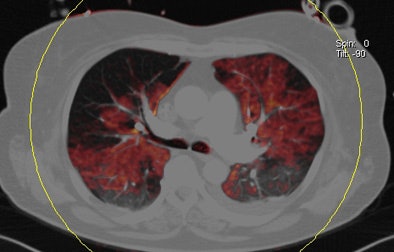

Dual-energy CT enables the selective display of iodine distribution within the pulmonary parenchyma following contrast-enhanced pulmonary CT angiography, which in turn permits the calculation of perfusion defect (PD) size in patients with suspected PE.

Depending on the shape and pattern of the defects at dual-energy CT, perfusion defects due to PE can generally be distinguished from, for example, patchy defects signaling other pathologies of the lung parenchyma, Bauer said.

The researchers measured perfusion defect size in the lung parenchyma caused by PE on dual-energy iodine distribution maps, and expressed it in two ways: as absolute quantification (VolPD in mL) and relative to the total lung volume (RelPD in %).

| Patient with bilateral segmental and subsegmental PE and large perfusion defects on dual-energy iodine distribution maps. All images courtesy of Dr. Ralf Bauer. |